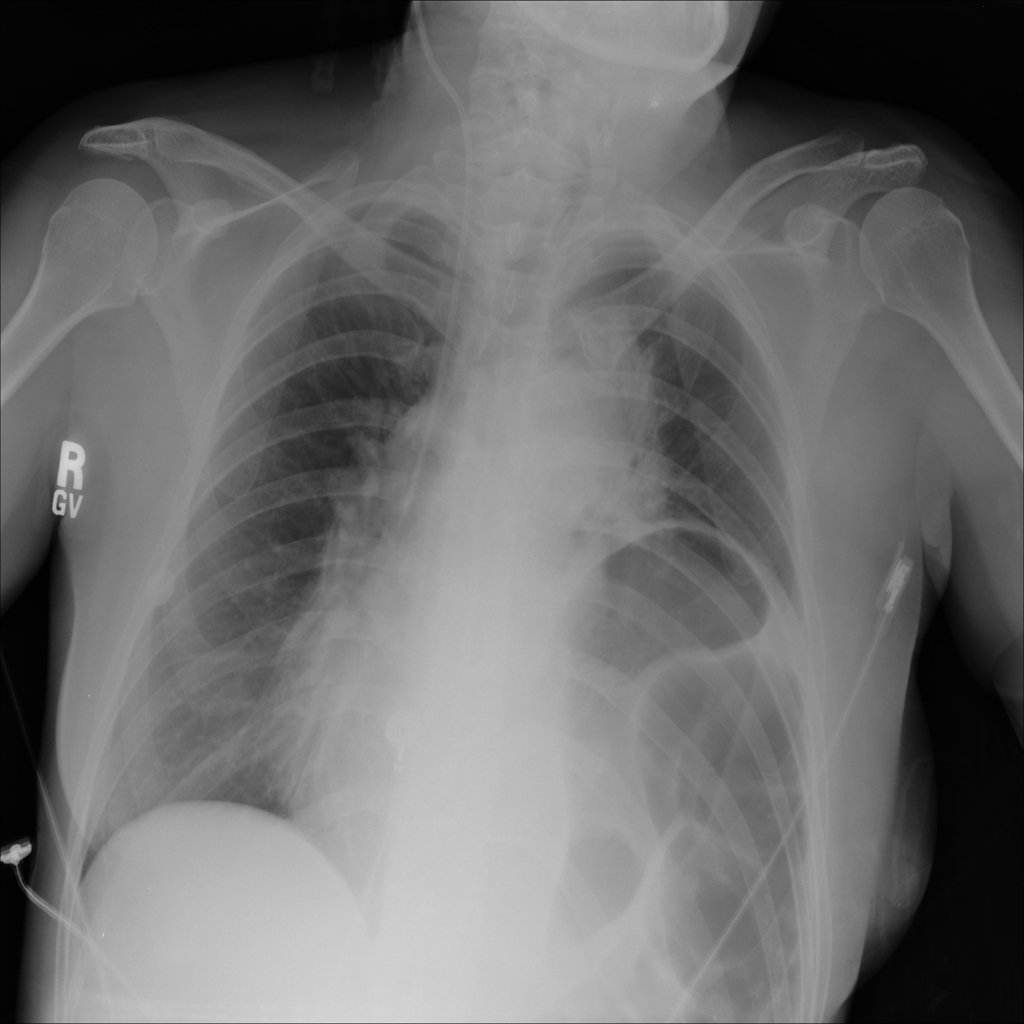

PAT-C048 · IMG-001Hernia

PAT-C048 · IMG-001

PA